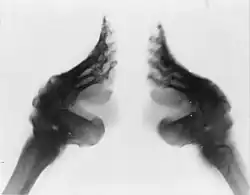

For centuries in Imperial China, smaller feet were considered to be a more aristocratic characteristic in women. The practice of foot binding was intended to enhance this characteristic, though it made walking difficult and painful.[54][55]

In China until the twentieth century, tiny, bound feet for women were considered aristocratic and feminine.